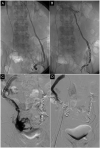

Interventional radiology is continuing to reshape current practice in many specialties of clinical care and the fields of gynecology and obstetrics are no exception. Imaging skills, clinical knowledge as well as vascular and non-vascular interventional technical ability, are essential to practice interventional radiology effectively. Patient safety is of paramount importance in interventional radiology as in all branches of medicine. Potential failures occur throughout successful procedures and are attributed to a spectrum of errors, including equipment unavailability, planning errors, and communication errors. These are mainly preventable by improved preprocedural planning and teamwork. Of all the targeted and effective actions that can be undertaken to reduce adverse events, the use of safety checklists might have a prominent role. The advantage of a safety checklist for interventional radiology is that it guarantees that human error in terms of forgetting key steps in patient preparation, intraprocedural care, and postoperative care are not forgotten.

Figures